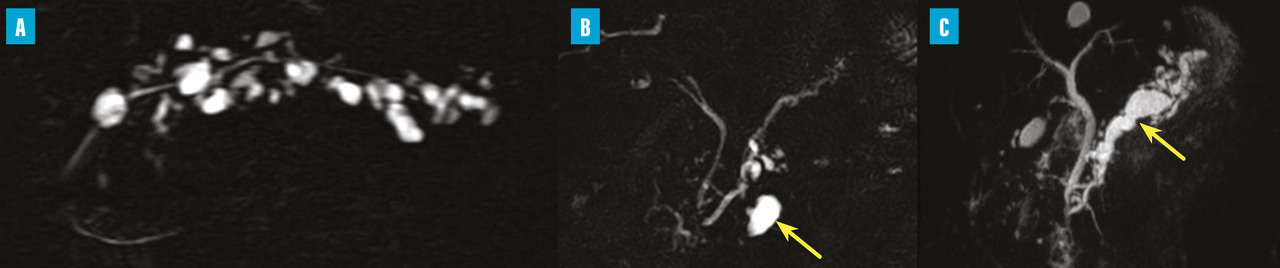

Il s’agit d’une tumeur kystique multiloculaire pouvant mesurer de 1 à plus de 20 cm, avec un aspect de «  cicatrice  » fibreuse centrale, parfois calcifiée (fig. 4). Ils sont plus fréquents chez les femmes (3 femmes pour 1 homme) avec un âge médian au diag­nostic autour de 60 ans. Ils sont le plus souvent de découverte fortuite ou secondaire à l’exploration de douleurs abdominales aspécifiques. Leur taille est stable dans le temps dans 60 % des cas, ou avec une croissance lente (4 mm/an). Les complications sont rares, et la dégénérescence exceptionnelle (moins de dix cas décrits dans la littérature), la surveillance n’est donc pas nécessaire. Pour les exceptionnelles lésions volumineuses (10 % de séreux macrokystiques), une chirurgie peut se discuter12 si elles sont à l’origine de symptômes invalidants.

Toujours parmi les LKP rares à potentiel malin, on compte les tumeurs neuro-endocrines (TNE) kystiques (20 % des TNE pancréatiques) [fig. 5]. De découverte fortuite et non fonctionnelles, les TNE kystiques sont uniques, uniloculaires, bien différenciées, de bas grade, c’est-à-dire avec un indicateur de prolifération Ki67 < 3 %, et la présence d’une masse hypervasculaire (nodule) au niveau de la paroi. La partie charnue tissulaire peut être de petite taille.